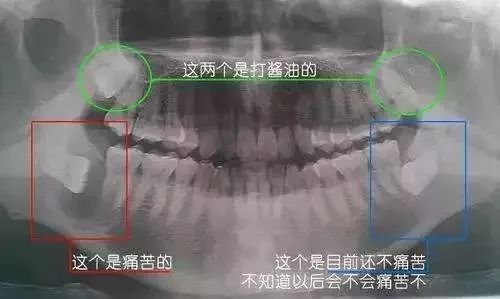

全景片(曲面斷層片)

影相全口牙齒,二維影像,可將全口牙齒的體層影像,雙側上下顎骨,上顎竅,耳頰關節同時顯示在一張膠片上。